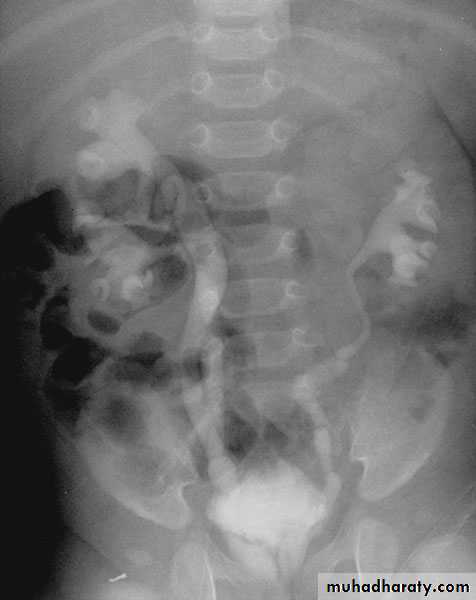

Ureteral duplication: partial and complete

Partial duplication: is more common. Two ureters draining single kidney for variable length, then unite together before entering the bladder in one ureteric orifice. Rarely the lower part is duplicated as inverted Y ureter.Complete duplication:

Less frequent, the whole ureter is duplicated, and each one opens in separate orifice in the bladder. The ureter draining the upper partopens more distally

in the bladder.

iComplete ureteral duplication and ectopic ureteric orifice.